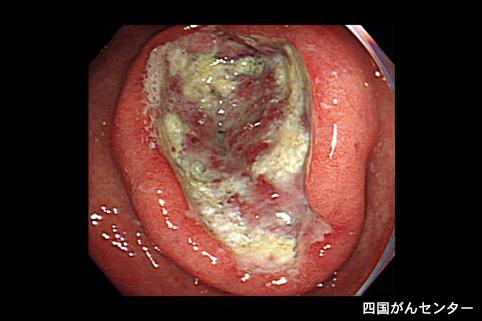

화학요법이 유효했던 위소세포암(내분비세포암) (증례제시:국립병원 시코쿠 암센터)

[Image-ID:3291]

질환(병리주체)의 분류

악성 상피성종양/기타

부위(장기별)

위(부위)/전정

검사방법

내시경

종양의 육안분류

2형(궤양국한형)/

종양의 최대경(밀리미터)

40이상